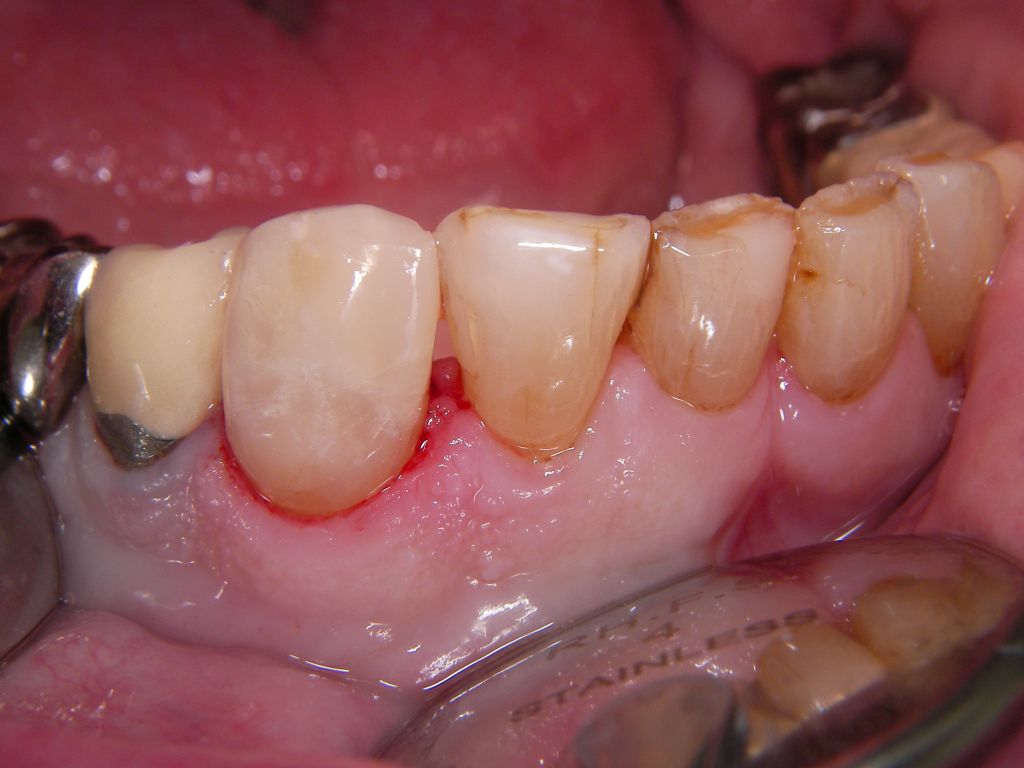

![]() | Der Eckzahn (Zahn 43) in der Mitte des Bildes zeigt an mehreren Stellen am Füllungsrand schwarze Karies, wie man hier aus verschiedenen Perspektiven sieht. Der Zahn rechts daneben auf dem Foto (Zahn 42) zeigt eine schwarze Randverfärbung einer älteren Kunststofffüllung. |

![]() | |||||||||||||||||||||||||||||||||||||||||||||||||||||||||||||||||||||||